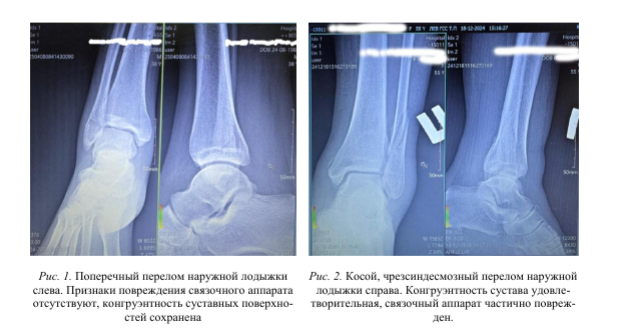

Однако, чаще всего требуется визуализация ГСС, для точного определения характера повреждений и планирования дальнейшего лечения. Рентгенография остаётся золотым стандартом благодаря своей доступности и информативности. В типичном случае достаточно рентгенографии в двух стандартных проекциях (переднезадней и боковой). Это следующий этап сортировки пациентов с травмой ГСС. После изучения рентгеновских снимков: часть пациентов остается на амбулаторном этапе (рис. 1, 2), а часть, с более серьезными травмами ГСС, направляется на лечение в стационар [3, 5, 9, 11, 13].

В первом случае (рис. 2), смещение наружной лодыжки произошло после уменьшения отека и снижения болевого синдрома. Возможно на стопу было произведено физическое, осевое воздействие, получить четкий, однозначный ответ от пациента не удалось.